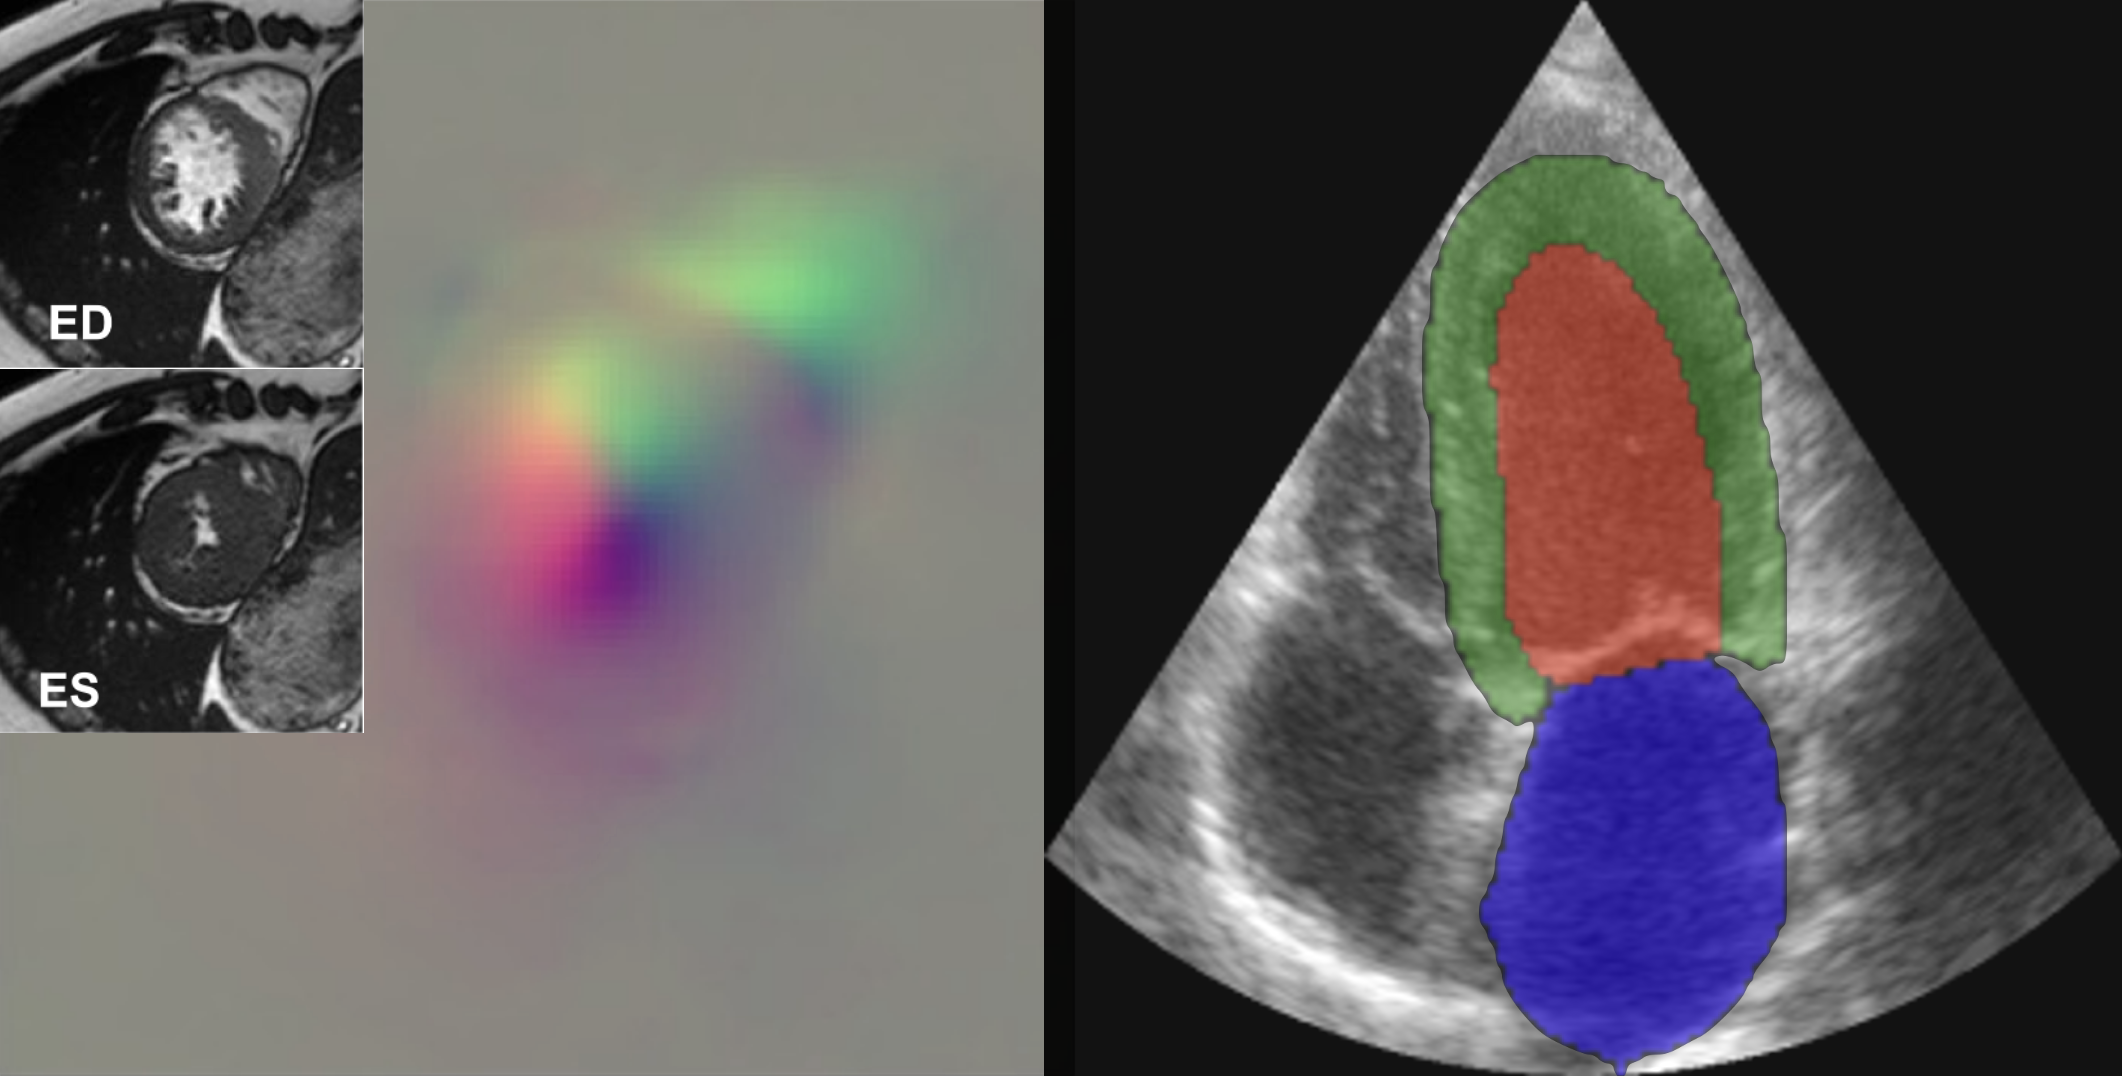

Every heart is unique—and so is heart disease. Standard cardiac MRI scans provide static snapshots, but they don’t fully capture how an individual heart moves and functions over time. Our project focuses on developing personalized digital twins of the heart by fusing multi-view cardiac MRI to reconstruct 3D+time heart shape and motion. These models enable predictive simulations of disease progression and treatment response, offering a powerful tool for personalized diagnosis and care.